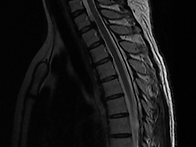

흉추 ,경추,요추 MRI

pinkmuhly486 25.09.191. 흉추 MRI : 등통증,소화불량,어깨결림 증상 있으나 병원에서는..